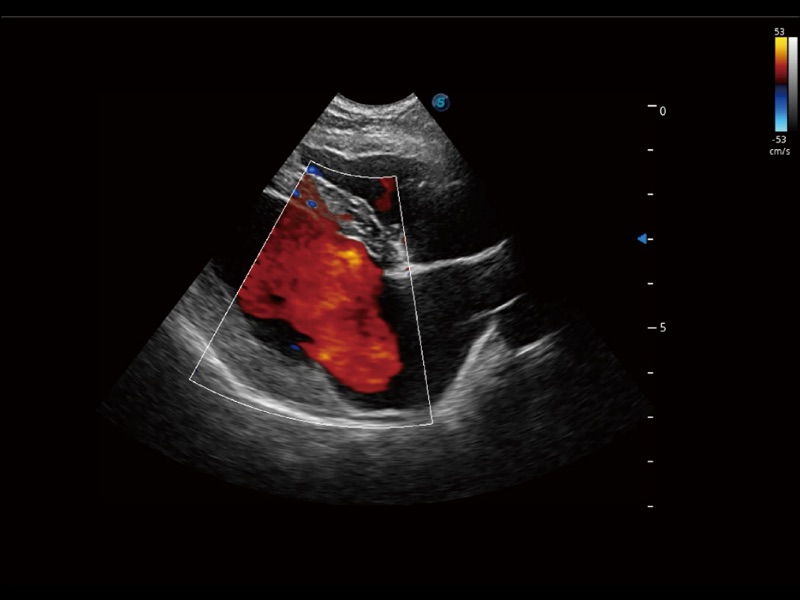

采用紅、橙、黃、綠、青、藍(lán)、紫這七種肉眼最為敏感的色彩,直觀地顯示組織內(nèi)血流灌注的時間先后信息,更精準(zhǔn)捕捉血流灌注走行細(xì)節(jié)。

通過創(chuàng)新的 Matrix E自適應(yīng)濾波器和超長時間域算法,極大提升超低速微細(xì)血流的檢出能力,同時更精準(zhǔn)地濾除軟組織和噪聲信號,為獸用醫(yī)生提供以往無法通過常規(guī)血流獲得的疾病診斷信息。

通過色彩血流和實(shí)時寬景相結(jié)合,可觀察到完整的靜脈或動脈的血流,方便醫(yī)生檢查。實(shí)時掃查過程中,如有任何操作失誤也可以很容易地進(jìn)行回掃擦除,而不會中斷掃查。

實(shí)時用顏色表示心肌組織運(yùn)動,觀察和定量組織的運(yùn)動情況,對快速檢測與評估心肌的灌注和活性、電傳導(dǎo)及心肌收縮和舒張功能等均能提供重要的診斷信息。